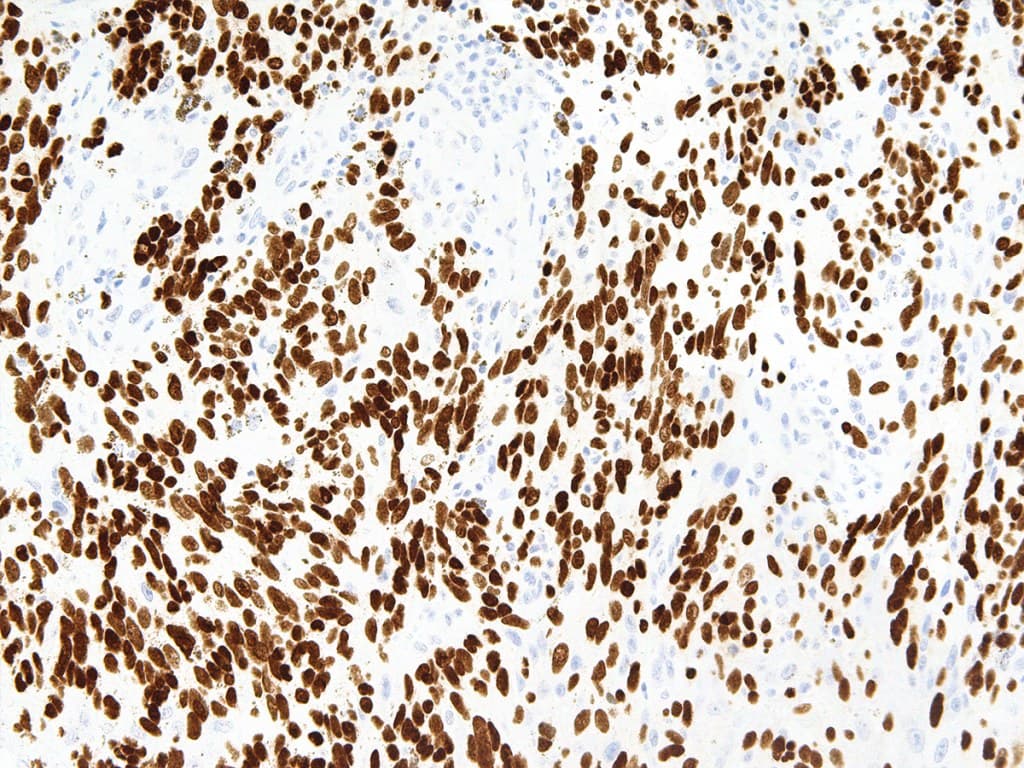

SRY (Sex Determining Region Y)-Box 10 (SOX-10), también conocido como factor de transcripción SOX-10, es un factor de transcripción nuclear que actúa en la regulación del desarrollo embrionario y en la especificación y diferenciación de las células de linaje melanocítico. Durante el desarrollo, SOX10 aparece por primera vez en la cresta neural en formación y continúa expresándose en las células de Schwann. Es importante para la diferenciación, maduración y mantenimiento de las células de Schwann y los melanocitos. SOX-10 se expresa de forma difusa en neurofibromas y schwannomas, y las mutaciones en el gen SOX-10 están relacionadas con las enfermedades de Waardenburg-Shah y Waardenburg-Hirschsprung. También se detecta en melanocitos y células epiteliales de glándulas salivales y mamarias. Los antiSOX-10 han demostrado ser sensibles al melanoma convencional, fusiforme y desmoplásico, y se han utilizado para detectar el melanoma metastásico y el nevus capsular ganglionar en los ganglios linfáticos centinela.

Sección de melanoma